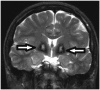

Molar Tooth Sign

In transverse CT or MRI images at the level of the midbrain, the appearance of a horizontal tubular structure originating from the midbrain on both sides of the midline, classically resembles, and is therefore defined, as a molar tooth sign (Fig. 21) (37). It is seen in Joubert syndrome, where this characteristic appearance is used to diagnose the disease with obstetric ultrasound (38).

caption a8Molar tooth sign.